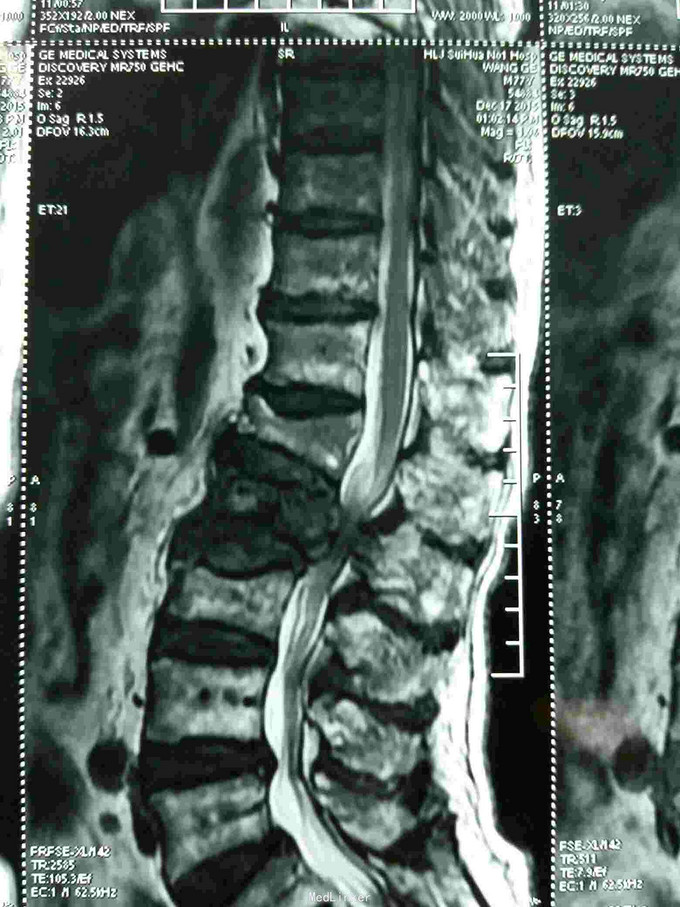

骨转移,溶骨性骨转移

腰椎骨转移一例

骨转移ct

骨转移片子

肺癌骨转移ct图片